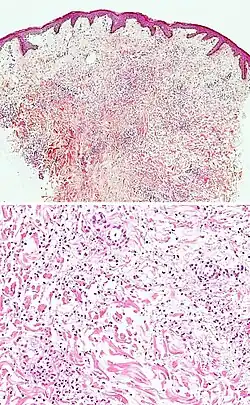

Generally/Not otherwise specified Typical findings, called "vacuolar interface dermatitis":[6]

• Mild inflammatory cell infiltrate along the dermoepidermal junction (black arrow in image)

• Vacuolization within the basal keratinocytes (white arrow in image)

• Often necrotic, predominantly basal, individual keratinocytes, manifesting as colloid or Civatte bodies